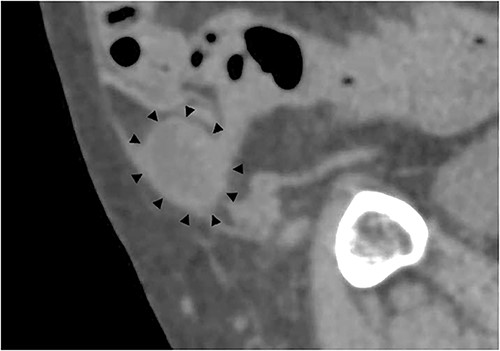

A 79-year-old male patient with a medical history of right inguinal hernia presented to the emergency department with right inguinal swelling and pain. We found the inguinal swelling, which extended toward the head, to be atypical. In addition, contrast-enhanced computed tomography (CT) scan revealed that a portion of the small intestine was incarcerated between the internal and external oblique muscles, and the hernia contents had prolapsed cranially from the hernial orifice. Furthermore, the sagittal view revealed that the contents of the hernia had prolapsed ventrally and not along the spermatic cord (Figs 1 and 2). Therefore, we diagnosed it as a right interparietal inguinal hernia, and laparoscopic hernia repair was planned. Owing to the fact that the manipulative reduction was difficult, we planned to release the incarceration first.

Sagittal section of contrast-enhanced CT; the black triangles indicate the incarcerated small bowel.